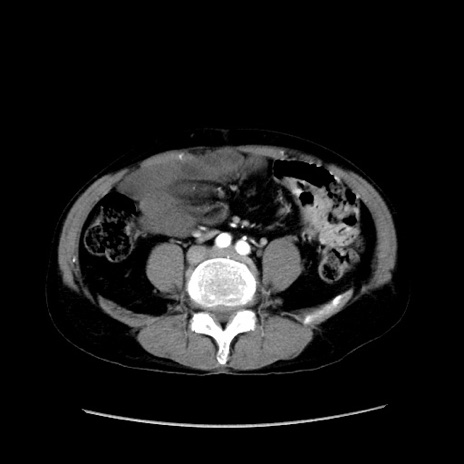

症例37(横断像)

【症例】40歳代 男性

【主訴】腹痛

【現病歴】4時間ほど前に電車に乗車中に臍部上より腹痛出現。徐々に増悪し起立困難となり、救急外来受診。生ものは数日食べていない。今朝お雑煮を食べた。

【身体所見】BT 36.8℃、BP 117/84mmHg、HR 91/min、SpO2 97%、苦悶様、腹部:臍上部広範囲圧痛あり、反跳痛±

【データ】WBC 8100、CRP 0.03